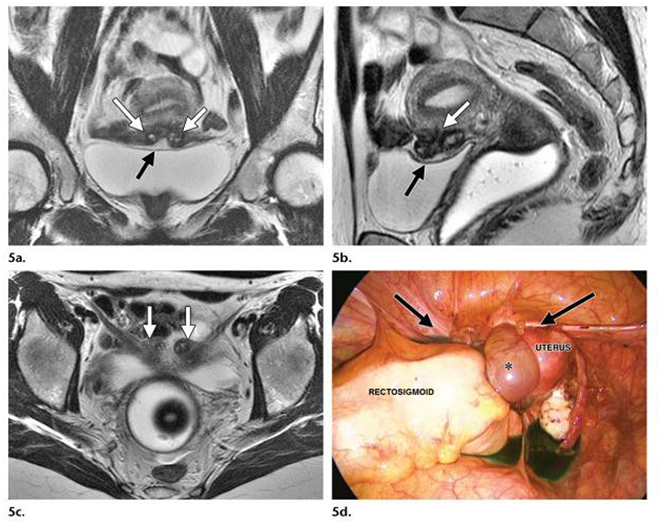

Hình 5. Lạc nội mạc tử cung ở dây chằng tròn hai bên, gần chỗ cắm vào tử cung

Hình 6. Lạc nội mạc ở sau cổ tử cung